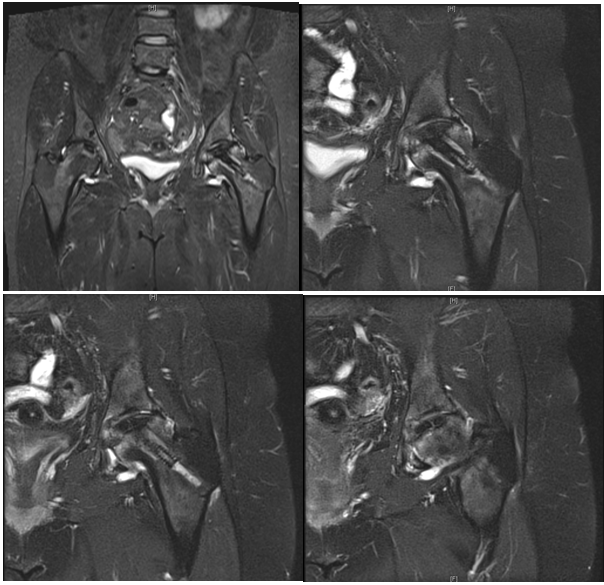

A 45-year old female was admitted with symptoms of joint pain of 1 year duration in both hips. The left was involved more than the right. The hip pain was so intense the patient could not carry on her routine duties. Her past medical history revealed a long history of Bronchial Asthma attacks requiring high dose of prednisone. Clinical evaluation minimal restriction of hip joint movement especially internal rotation. Plain radiographs of the pelvis were normal with Bilateral femoral head avascular necrosis is present with no collapse on the left hip (Figure 1), whereas an MRI scan revealed the avascular necrosis involves an area measuring 3.9 cm mediolateral x 3.8 cm AP. There is mild edema in the left femoral head and neck. No subchondral bone depression identified overlying the avascular necrosis at the left hip.

Figure 1 Preoperative AP of both hips and Lateral radiograph of left avascular necrosis changes with a sclerotic rim and no femoral head flattening.